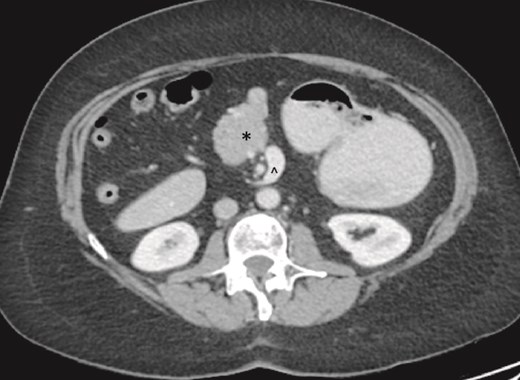

On examination, the abdomen was soft but mildly distended. Bowel sounds were heard, and the epigastrium was mildly tender. Standard bloodwork was normal. Review of an abdominal computerized tomography (CT) scan from 4 years prior showed congenital malrotation of the bowel, with the small bowel to the left of the midline and colon entirely to the right (Fig. 1). There was partial agenesis of the dorsal pancreas (Fig. 2), azygous continuation of the inferior vena cava (IVC), a retroaortic and retrocrural left renal vein, and an unremarkable spleen alongside some splenules. The PV traversed anterior to the first part of the duodenum (Fig. 3). There was relative narrowing of the distal stomach and the duodenum was nondilated.

Partial agenesis of the dorsal pancreas (*). Superior mesenteric vein (^) seen to the left of the superior mesenteric artery.

Preduodenal PV seen crossing the duodenum (D) causing partial obstruction.